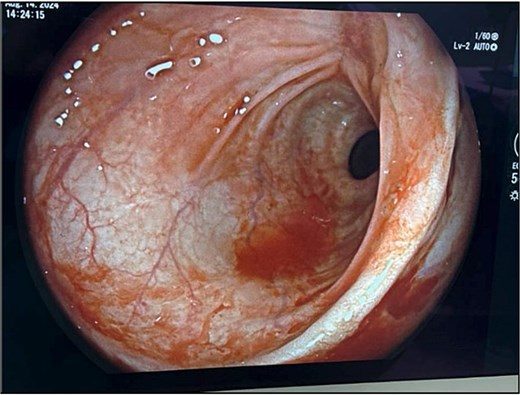

The patient’s leukocytosis resolved during hospitalization, and she was discharged on hospital day 5 with dietary modifications, including a low-fiber diet. At 4-week follow up, flexible sigmoidoscopy demonstrated near-complete healing of the rectal perforation, with only minimal residual mucosal disruption (Fig. 3). By 6 weeks post-injury, follow-up flexible sigmoidoscopy confirmed complete mucosal healing and restoration of normal rectal wall architecture, though mild rectal stenosis persisted (Fig. 4). The patient remained asymptomatic with resolution of her initial symptoms.

Follow-up flexible sigmoidoscopy at 4 weeks showing near-complete healing of the rectal perforation, with a small residual mucosal disruption.